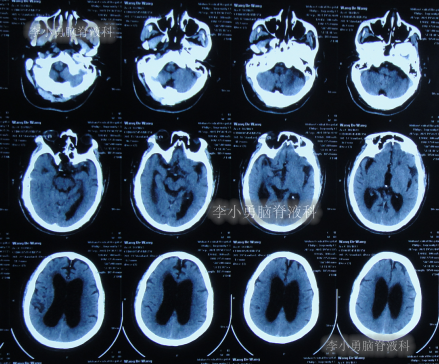

2020年10月29日(发病已8年),因症状一直没有得到改善且呈进行性加重趋势,查头部核磁示脑积水(图-1)。

图-1:2020年10月29日头部核磁

发现脑积水后8天即2020年11月6日,就诊于第2家的上海的某三甲医院,入院后再次检查(图-2)后诊断为正常压力脑积水。

图-2:2020年11月11日头部核磁